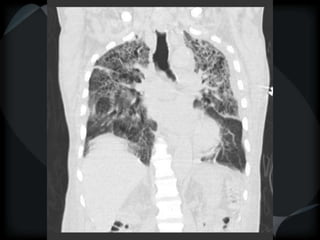

Emphysema - CL

Emphysema - PA

CL + PS emphysema

Hyperlucency

Centrilobular emphysema

Paraseptal emphysema

Panacinar emphysema

HRCT - ILD/DPLD Nodular PLLH Sarc/Berylliosis Mets Silicosis Miliary TB Lymphoma Kaposi Bronchiolar SAHP RB-ILD LCH Bronchiolitis Acinar fibrosis /Reticular/Honeycomb UIP CHP Asbestosis NSIP AIP Septal / Interlobular Venous Lymphatic CHF LC MS Lymphoma PVOD Acinar filling/ ground glass COP CEP Alveolar proteinosis Alveolar microlithiasis DIP AIP SAHP AHP BAC Hyperlucency Centrilobular emphysema Paraseptal emphysema Panacinar emphysema Cystic Parenchymal Bronchiectasis LCH LAM LIP